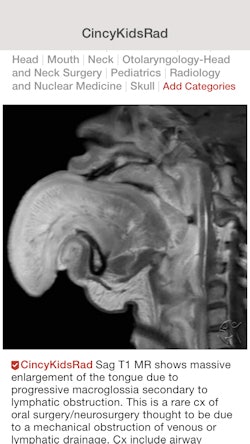

Groups can also set up accounts on Figure 1; one of the most popular radiology groups is run by the department of radiology and medical imaging at Cincinnati Children's Hospital and provides pediatric radiology education.

Based on feedback recently received from a radiologist, Figure 1 is looking to incorporate updates to improve usability in the type of lighting environments that radiologists typically work in. In other radiology-oriented developments, Figure 1 also plans to reorganize specialties.

"Currently, on our platform, all radiologists and nuclear medicine physicians are together, and we're going to be splitting up those specialties so that people can self-identify," he said.